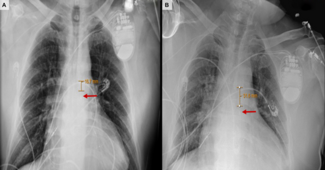

The COVID-19 pandemic has imposed challenging scenarios, necessitating a “thinking outside the box” approach for patients with profound respiratory failure requiring mechanical ventilation in the prone position.